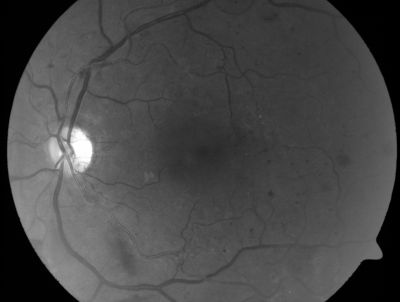

PDR - Mild Vitreous Hemorrhage and Good Vision

58-year-old woman has diabetic retinopathy in both eyes with neovascularization of the optic nerve, worse in the right eye than the left eye.  She has had panretinal laser in both eyes and vitreous hemorrhage in the left eye.  Her vision, since I saw her last in June, is about the same.

VISUAL ACUITY:  Vision OD is 20/25, OS is 20/20.